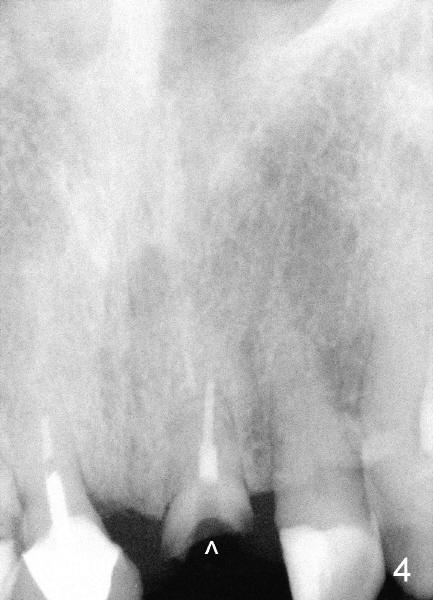

Sixty-five year old man is a bruxer, as shown in Fig.1, 2 (upper. lower arch, respectively, mirror view).  He has a night guard.  Fig.1-3 and Fig.4,5 are taken before and after crown fracture of the tooth #9, respectively.  It appears that the tooth is nonsalvageable.

Although gutta percha of #9 is overfilled, there is no active infection (Fig.3,4).  Can we place an implant immediately after extraction without loading or minimal loading?